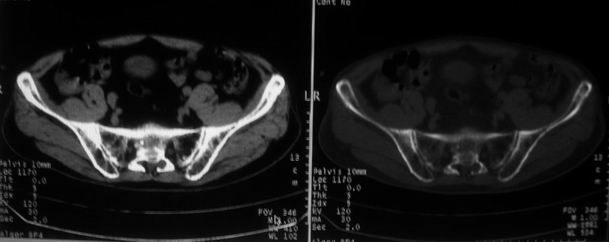

男,85岁,排尿困难。骶椎有问题吗?

前列腺明显增大,突入膀胱,各叶比例协调,密度均匀,精囊腺及精囊角正常;考虑良性增大。

这个病人排尿困难应该是前列腺增生造成的,ct对前列腺增生及前列腺癌诊断有一定限度,只能判断前列腺增大,建议还是做一个mr来鉴别一下增生或癌更好,因为增生多发生于中央带,癌多发生于周围带,而mr t2加权图像上中央带和周围带的信号有区别,因此诊断价值更高一些。

1)考虑前列腺增生症并阻塞性膀胱炎。2)骶椎右侧类似囊状骨质密度减低区,边缘骨质硬化,其内为软组织密度影填塞,相邻之骶椎椎管受压变形;考虑为骶椎右侧囊肿或神经纤维瘤。

建议:行mri检查。

1)前列腺明显增大,突入膀胱,各叶比例协调,密度均匀,精囊腺及精囊角正常;考虑前列腺增生症并阻塞性膀胱炎。2)骶椎右侧类似囊状骨质密度减低区,边缘骨质硬化,其内为软组织密度影填塞,相邻之骶椎椎管受压变形;考虑为骶椎右侧囊肿或神经纤维瘤。